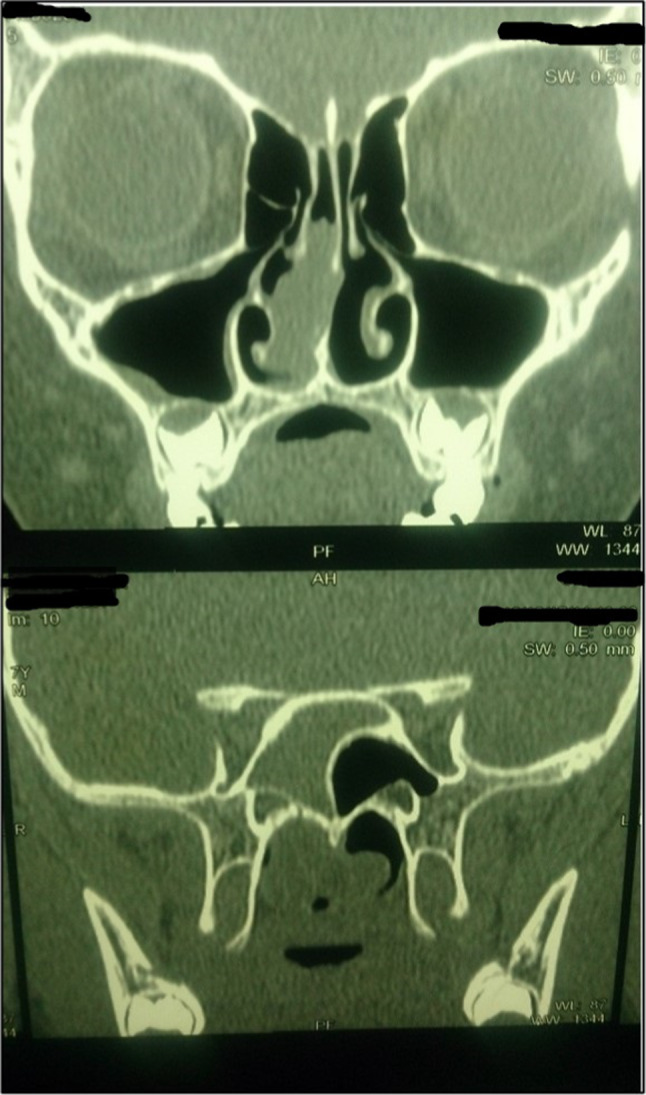

The differential diagnoses included choanal polyp, meningoencephalocele and granulomatous lesion. CT scan of the nose and sinuses showed homogenous soft tissue density involving right sphenoid sinus, extending to the right nostril and bilateral choanae, with no evidence of bony erosion or intracranial connection (Fig. 1).

Fig. 1.

CT images showing soft tissue density involving right sphenoid sinus and choana, without bony erosion